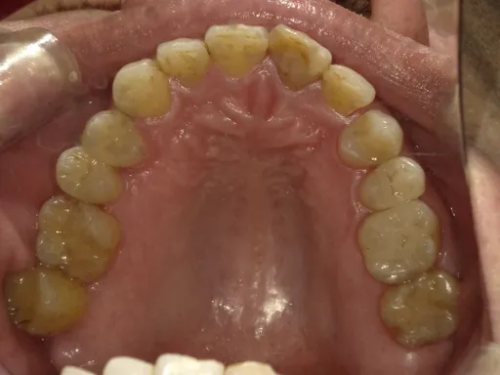

2026年05月15日

ホワイトニング 審美治療 症例集

出来るだけ早く歯を白くしたい方へ

「写真を撮った時に歯の黄ばみが気になる…」

「大事な予定があるから、できるだけ早めに白くしたい……